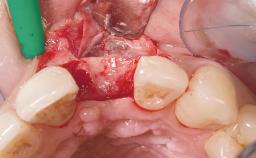

Late Placement of an Implant in a Maxillary Left Central Incisor Site

Bone Augmentation Horizontal|Staged

Augmentation Materials Xenogenous|Membrane

Soft Tissue Grafting Simultaneous

Placement Protocol Early or late implant placement